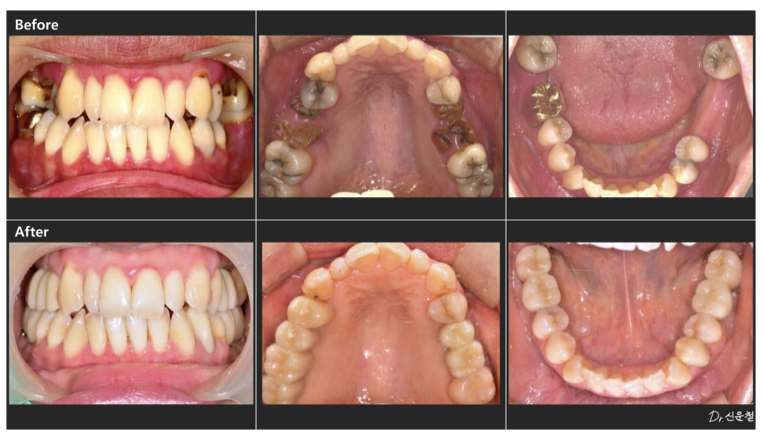

실제로 내원하신 30대 여성 환자분도

“아프진 않아요.”라고 말씀하셨습니다.

촬영일 250327

하지만 정밀 검진 결과, 깊게 진행된 사랑니 충치 뿌리만 남은 치아

잇몸뼈가 녹아 흔들리는 어금니 가 확인되었습니다.

통증이 없었던 것뿐,

문제는 이미 상당히 진행된 상태였습니다.

만약 웨딩 촬영 직전 증상이 악화됐다면

발치를 먼저 해야 하는 상황이었을 수 있습니다.

앞니 배열만이 아니라 어금니 충치, 보철 색감, 잇몸 라인까지

전체적인 밸런스를 함께 봐야 합니다.

디에스다솜치과에서는

단순히 “보이는 앞니”만이 아니라

웃는 순간 전체가 자연스러운지를 기준으로 진단합니다.

사용된 사진은 환자분의 동의를 받고 촬영 및 게재된 자료 이며 치료 기간은 환자의 구강 상태 및 계획에 따라 달라질 수 있습니다.

[진료일 2025.03.27 - 2026.01.12]